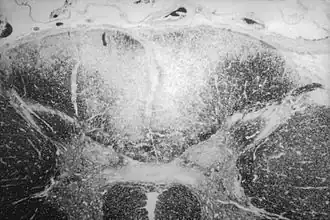

| Secção axial da medula espinhal mostrando a destruição causada pela sífilis (área esbranquiçada, no região central superior) das colunas posteriores, que carregam informação sensorial do corpo em direção ao cérebro | |